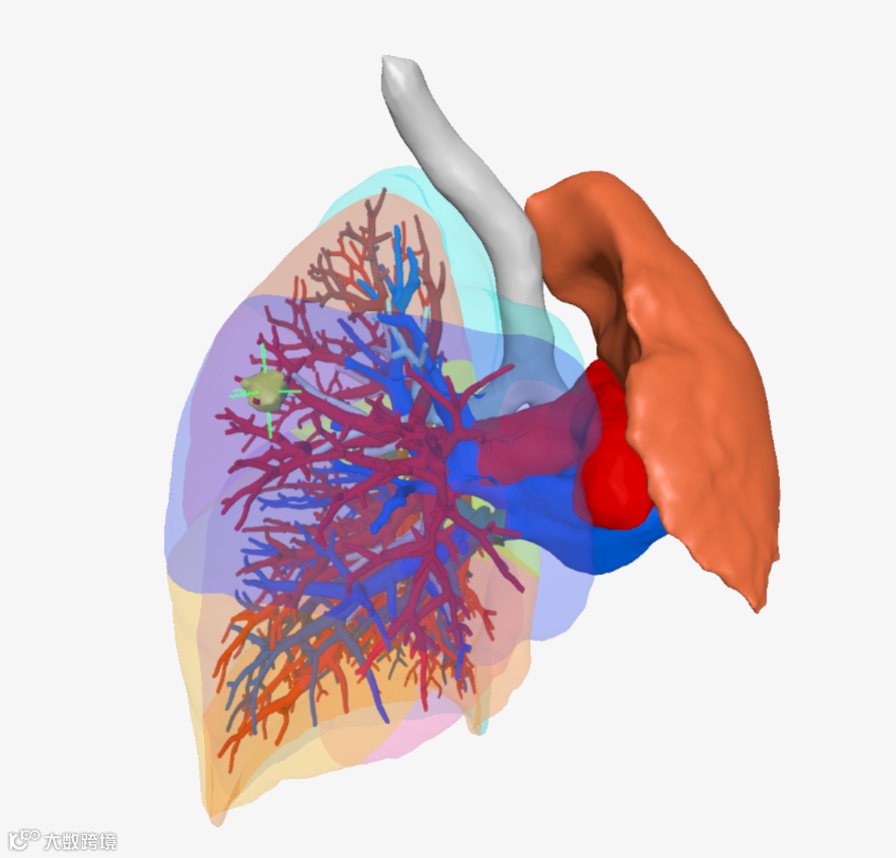

▲▲▲三维重建肺叶肺段

▲▲▲三维重建支气管

▲▲▲三维重建血管

该院胸外科手术团队用瀚依科技的AI三维重建服务,真实还原了结节的大小、位置和深度,全方位、多维度地观察了患者结节的空间位置、结节与周遭脏器粘连程度、结节对血管的侵占情况,并对手术需要的重要信息进行精准定量分析。